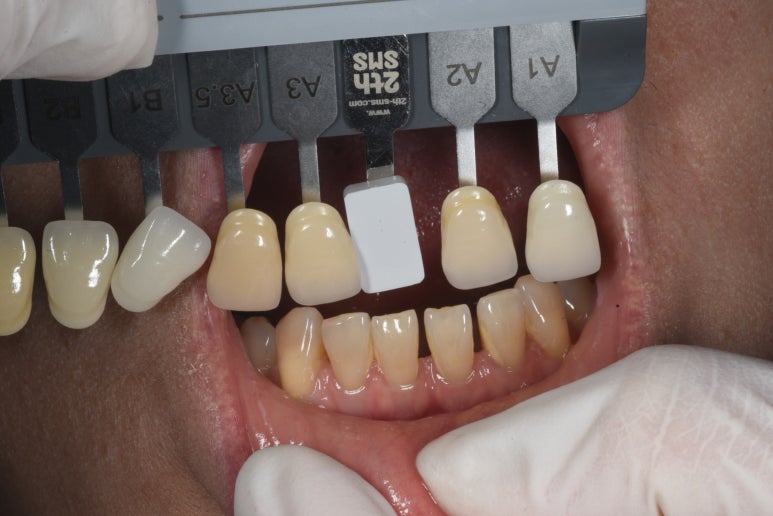

자, 이제 라미네이트 치료 과정을 살짝 볼까요?

먼저 치아를 다듬기 전에 치아 색상을 측정해둡니다.

이 과정에서 환자분이 원하시는 치아의 색상과 모양을 기록해둡니다.

저희 압구정 레브치과에서는 치아의 모양과 색상을 상담하는 과정에서 주치의와 전담 세라미스트가 함께 참여하여 환자분의 니즈를 파악하기 위해 노력합니다.

이 과정이 가장 중요합니다!!! 환자분이 어떤 치아를 아시는 지 정확히 파악해야 여러번 치과에 오시지 않게 되거든요. 한 번에 잘 만들어드리기 위한 과정입니다 :)